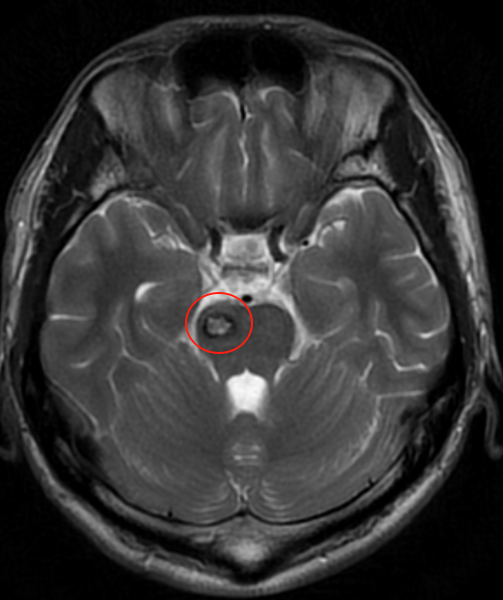

2025年1月,江先生因右侧丘脑、中脑及桥脑海绵状血管瘤突发出血,病情危急:持续头痛、视物模糊、肢体麻木疼痛无力、不能行走,一家人将他从河北120紧急转运到苏州。从咨询巴教授到手术顺利完成,仅用了短短3天时间。

对病患而言,“黄金手术时间”的宝贵性不容小觑。脑干海绵状血管瘤常常暗藏危机,首次出血症状轻微,保守观察却遭遇二次出血的致命反扑,症状急剧恶化、甚至需紧急医疗转运。“找到巴教授,想要抓住那重获新生的一线希望!”从术前无法行走,到如今的正常生活,这不仅凝聚着全家人的坚持与付出,更得益于巴教授成功实施的高难度手术。